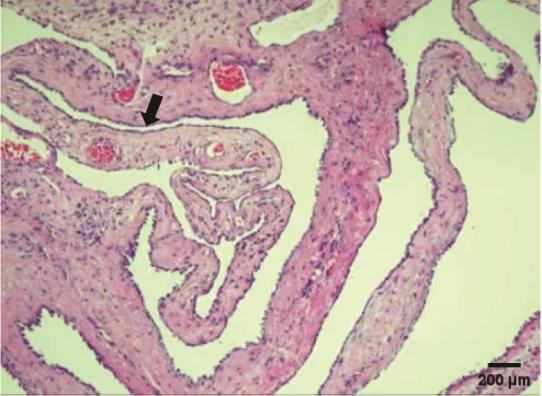

Noiret B, Renaud F, Piessen G, et al. Multicystic peritoneal mesothelioma: a systematic review of the literature[J]. Pleura Peritoneum, 2019, 4(3):20190024. doi: 10.1515/pp-2019-0024.

Zhang CH, Yu JW, Luo M. Multicystic peritoneal mesothelioma: A short review[J]. Curr Probl Cancer, 2017, 41(5):340-348. doi: 10.1016/j.currproblcancer.2017.03.002.

Incesu MM, Ucar M, Kozan R, et al. Benign Multicystic Peritoneal Mesothelioma: Two Rare Cases and Review of the Literature[J]. Curr Med Imaging, 2023 Nov 7. doi: 10.2174/0115734056246439231023111720.Epubaheadofprint.

Oshikiri H, Ozawa Y, Suzuki O, et al. Benign multicystic peritoneal mesothelioma occurring in bilateral inguinal canals metachronously: a case report[J]. Surg Case Rep, 2022, 8(1):44. doi: 10.1186/s40792-022-01399-5.

Ceylan AT, Maila A, Aziz Hakki C, et al. Benign multicystic peritoneal mesothelioma mimicking mucinous ovarian neoplasm with pseudomyxoma peritonei[J]. BMJ Case Reports, 2023, 16(3):e254116. doi: 10.1136/bcr-2022-254116.

Wu CC, Bassi A, Onitilo A, et al. Intra-Operative Diagnosis of Benign Multicystic Peritoneal Mesothelioma: A Case Report of Rare Entity and Lessons Learned[J]. Cureus, 2024, 16(5):e60664. doi: 10.7759/cureus.60664.

Wassef J, Kim J, Farag T, et al. A case of benign multicystic peritoneal mesothelioma[J]. J Surg Case Rep, 2024, 2024(10):rjae629. doi: 10.1093/jscr/rjae629.